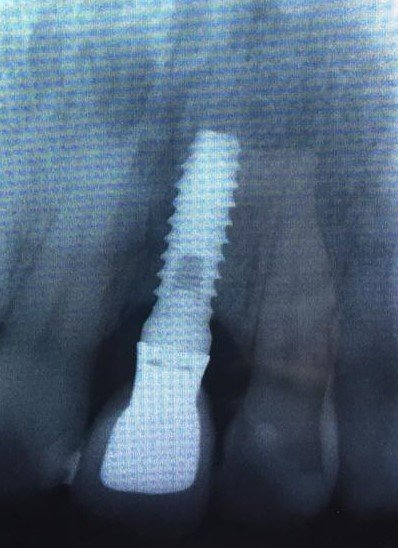

Buenas tardes, Necesitamos averiguar la marca del Implante en 46. Según nos dice el Paciente se lo puso en 2017. Muchas gracias. Un saludo.

son de conexión externa pero desconozco qué marca y con qué serían compatibles para tomar medidas y hacer protesis